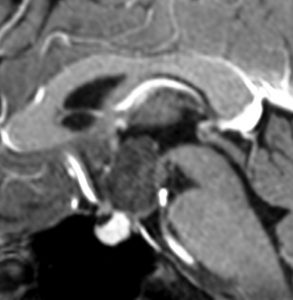

全く何もしなくても良い成人の毛様細胞性星細胞腫

20代女性に偶然発見された視床下部(第3脳室)腫瘍です,T1低信号,T2で高信号,右側のガドリニウム造影では全く増強されません。毛様細胞性星細胞腫と診断できます。眼科での視野検査で視野欠損はありませんでした。生検術もなにもせず経過をみました。

左が初診時,右が5年後のMRI画像です。腫瘍の大きさは全く同じです。このような腫瘍はしばしば経験します。慌てて生検術や開頭手術など計画しないで,画像診断をしっかりすることが大切です。